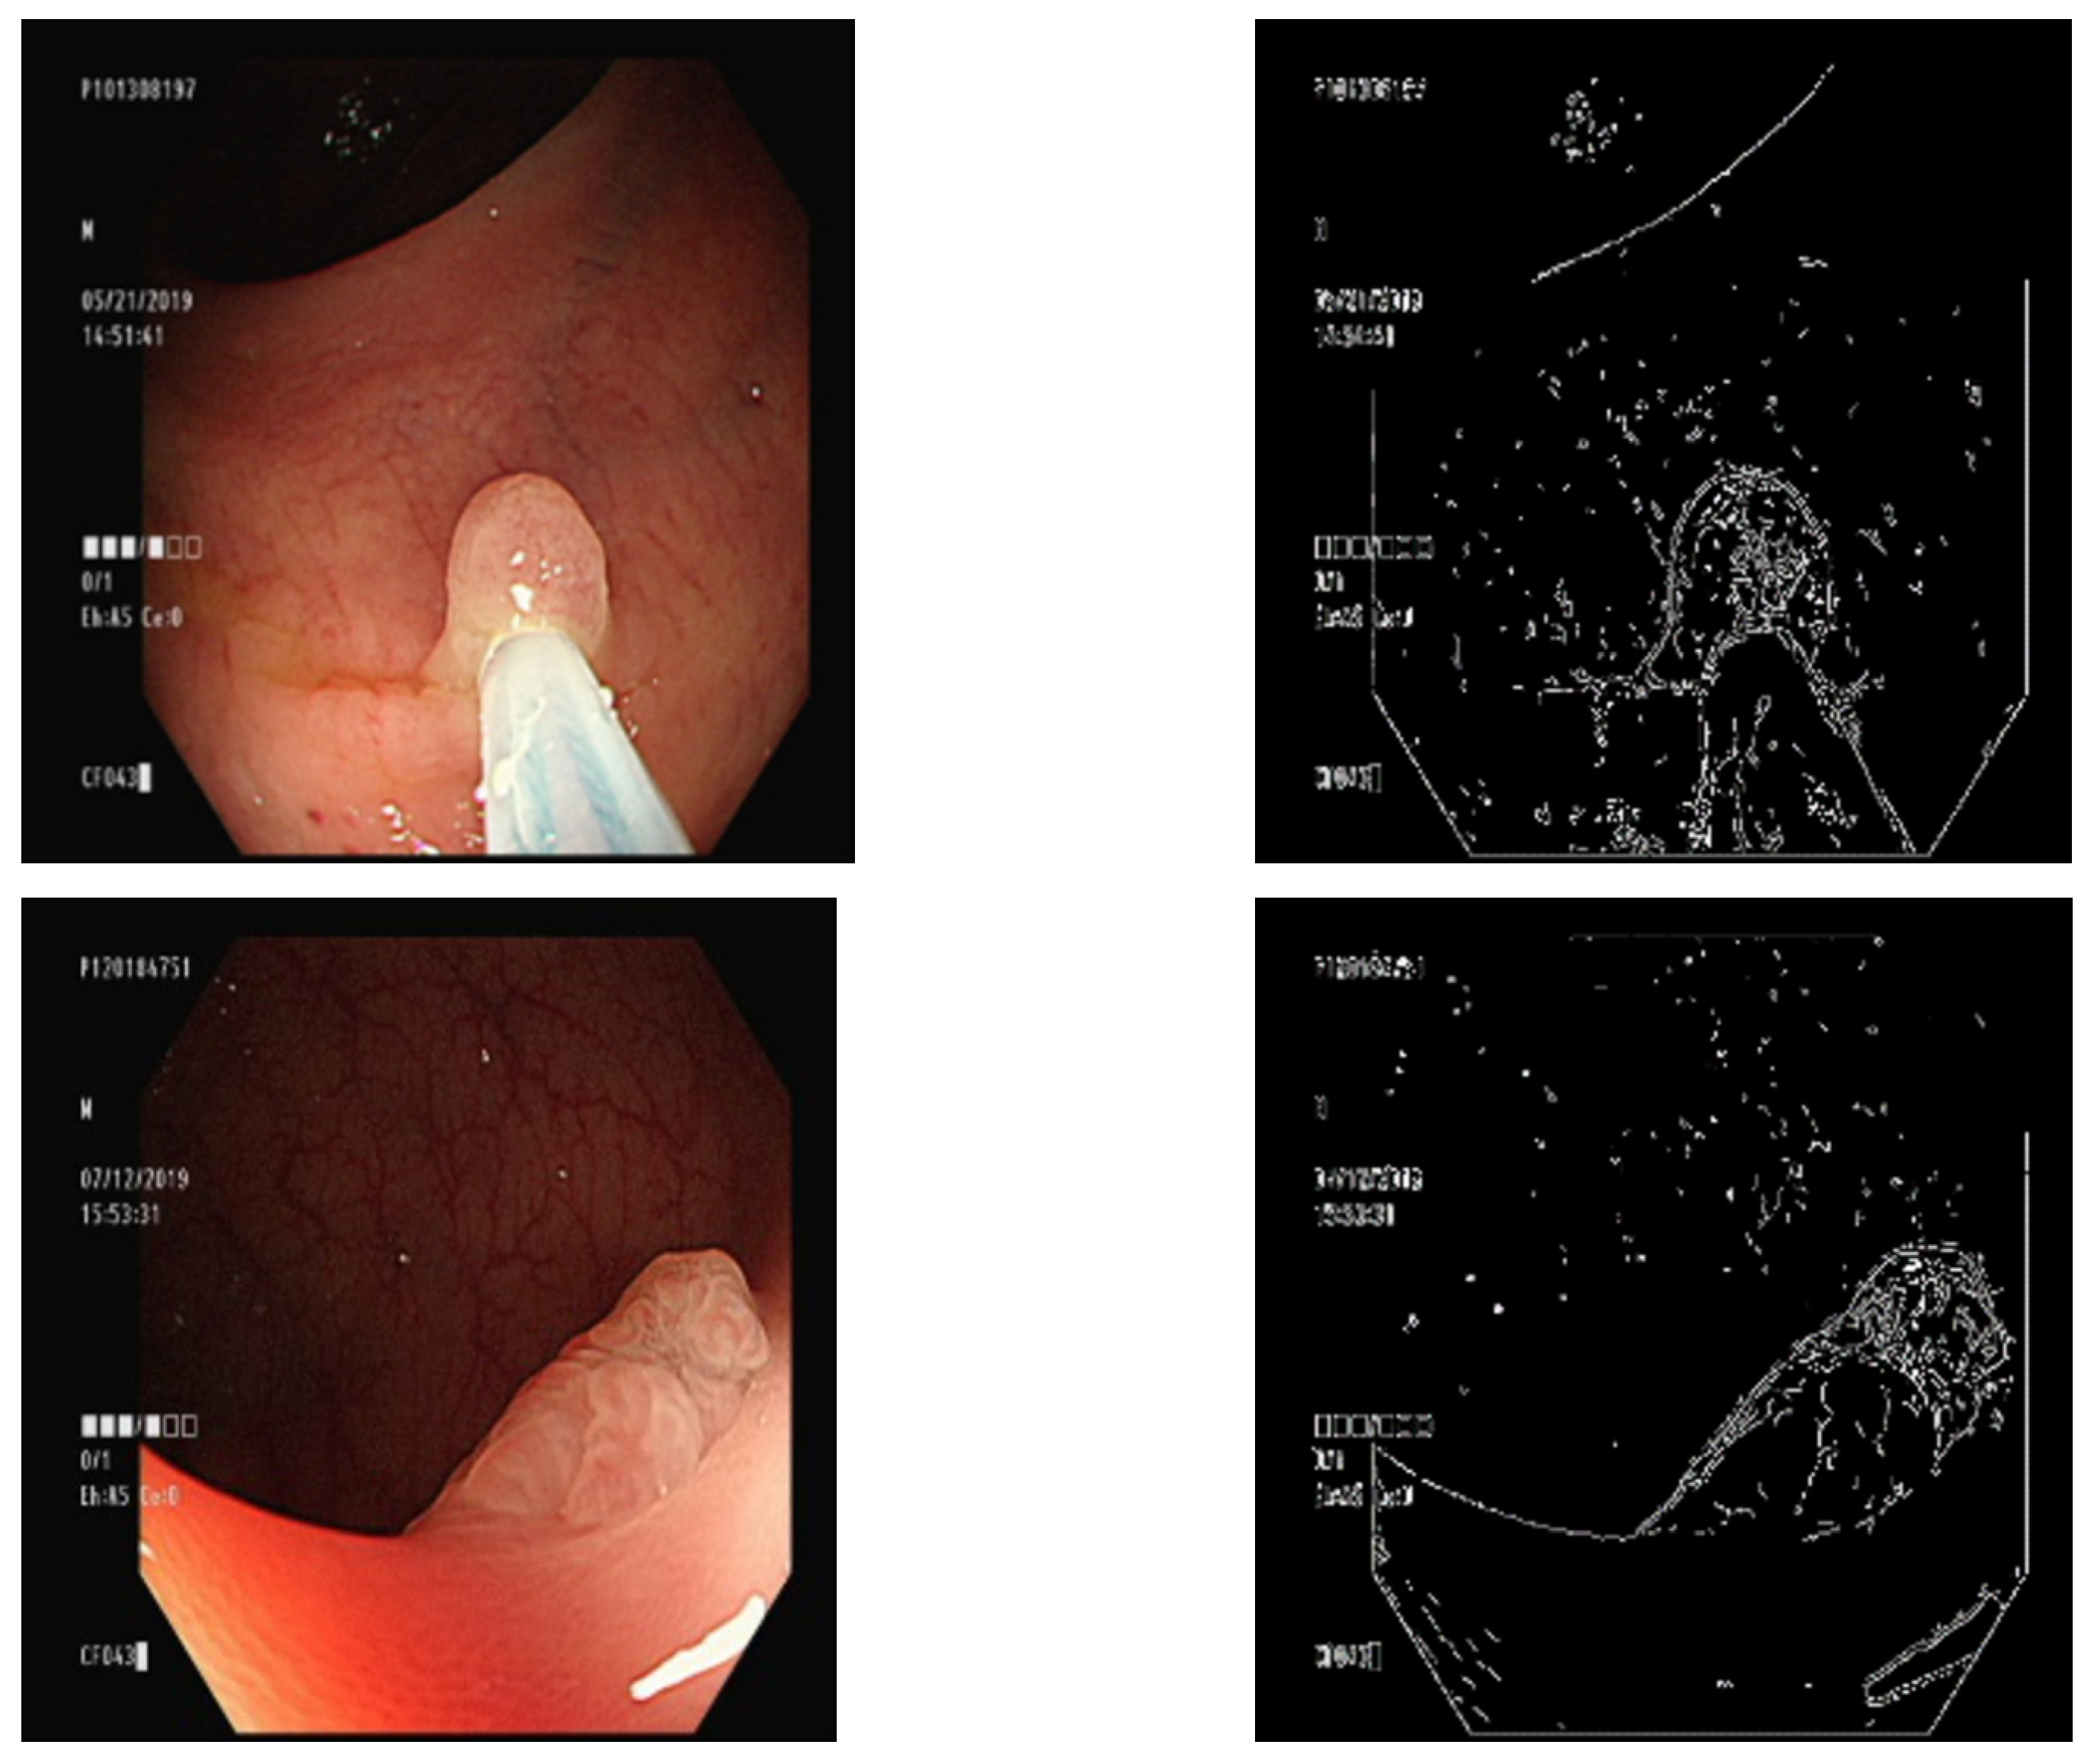

3.3. Finding Contours Using the Canny Algorithm

3.4. Overlaying a Contour Map on a Ground Truth Map

3.5. Overlaying the Ground Truth Map onto the Original Image